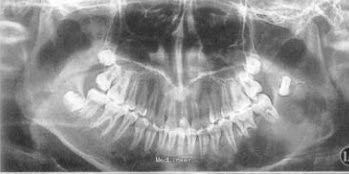

男, 23 岁。因下领骨肿物而来院就诊, 3个月前无何诱因左下领部肿胀隆起, 左下唇有麻木感及不适。家族无类似病史。

体检: 领面不对称左下领骨隆起, 左下6、7、8 牙前庭均突出, 但无松动。X 线检查: 左下领骨见有7.o x 8.s c m 圆形分隔透光区, 边缘呈分叶状改变。其中可见间隔线及致密硬化带, 牙根尖部有骨质吸收. 诊断: 左下领骨造釉细胞瘤

左侧下颌骨成釉细胞瘤 处理:全部下手术切除。 手术所见: 肿瘤侵及左下第4 牙、下领骨升支及切迹部, 腔内有多量较粘稠的白色干酪样物质。 病理所见: 囊壁由致密的纤维组织构成, 其内有大量琳巴细胞及浆细胞浸润, 内衬有增生的鳞状上皮及角化物质。病理诊断: 左下领骨角化囊肿